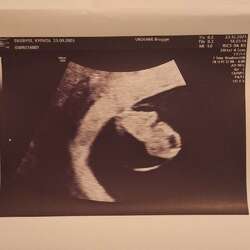

12 weken 🩵🩷 Op het bovenste beeld zie je een handje 😍